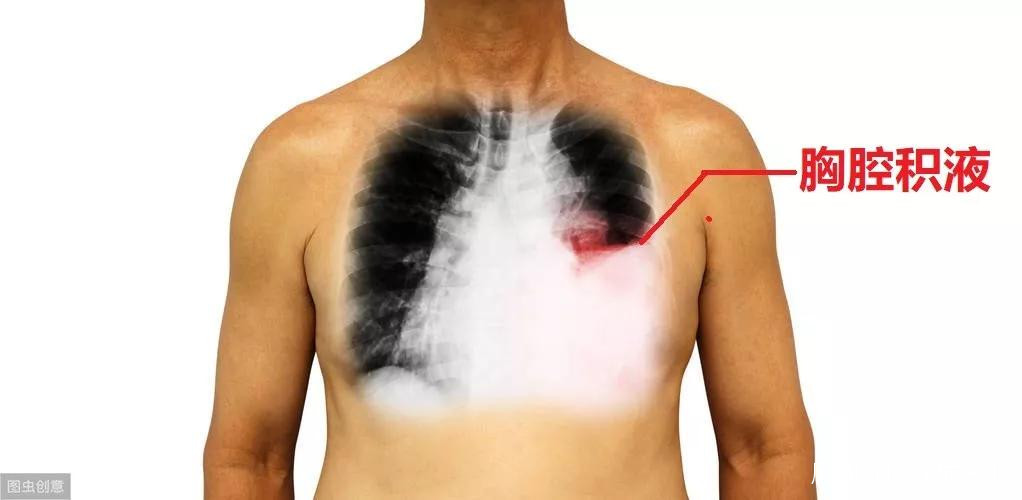

如果患者有肺炎、肺癌、肺結核,或者心力衰竭等,可能導致胸腔積液。所謂的胸腔積液,就是在胸腔裏面積聚了液體。正常情況下,胸腔不應該有很多液體的,僅有一點點液體而已。但疾病狀態下,比如肺癌,滲出液體會很多,這些液體就會落入胸腔,導致胸腔積液,或者積血。

胸腔積液的存在,會影響肺膨脹,影響通氣,患者會覺得缺氧、氣不夠。為了解決這問題,我們需要進行胸腔穿刺術,把裏面的液體抽出來。同時,可以把液體拿去化驗,瞭解液體的性質,從而推測產生胸腔積液的病因。再針對病因治療。

胸腔穿刺的過程比較簡單,就是在兩根肋骨之間進針,直接懟入胸腔裏面,如果有液體出來,那就説明穿對地方了。很少情況下,可能會穿到血管,造成大出血。也可能穿到肺,把肺給捅破了,導致氣胸。為了預防這些併發症,醫生需要打起12分精神,嚴格按照操作規程。